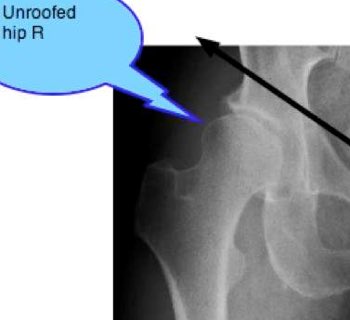

Have you had an xray of your hips?

5. Hip xray report.